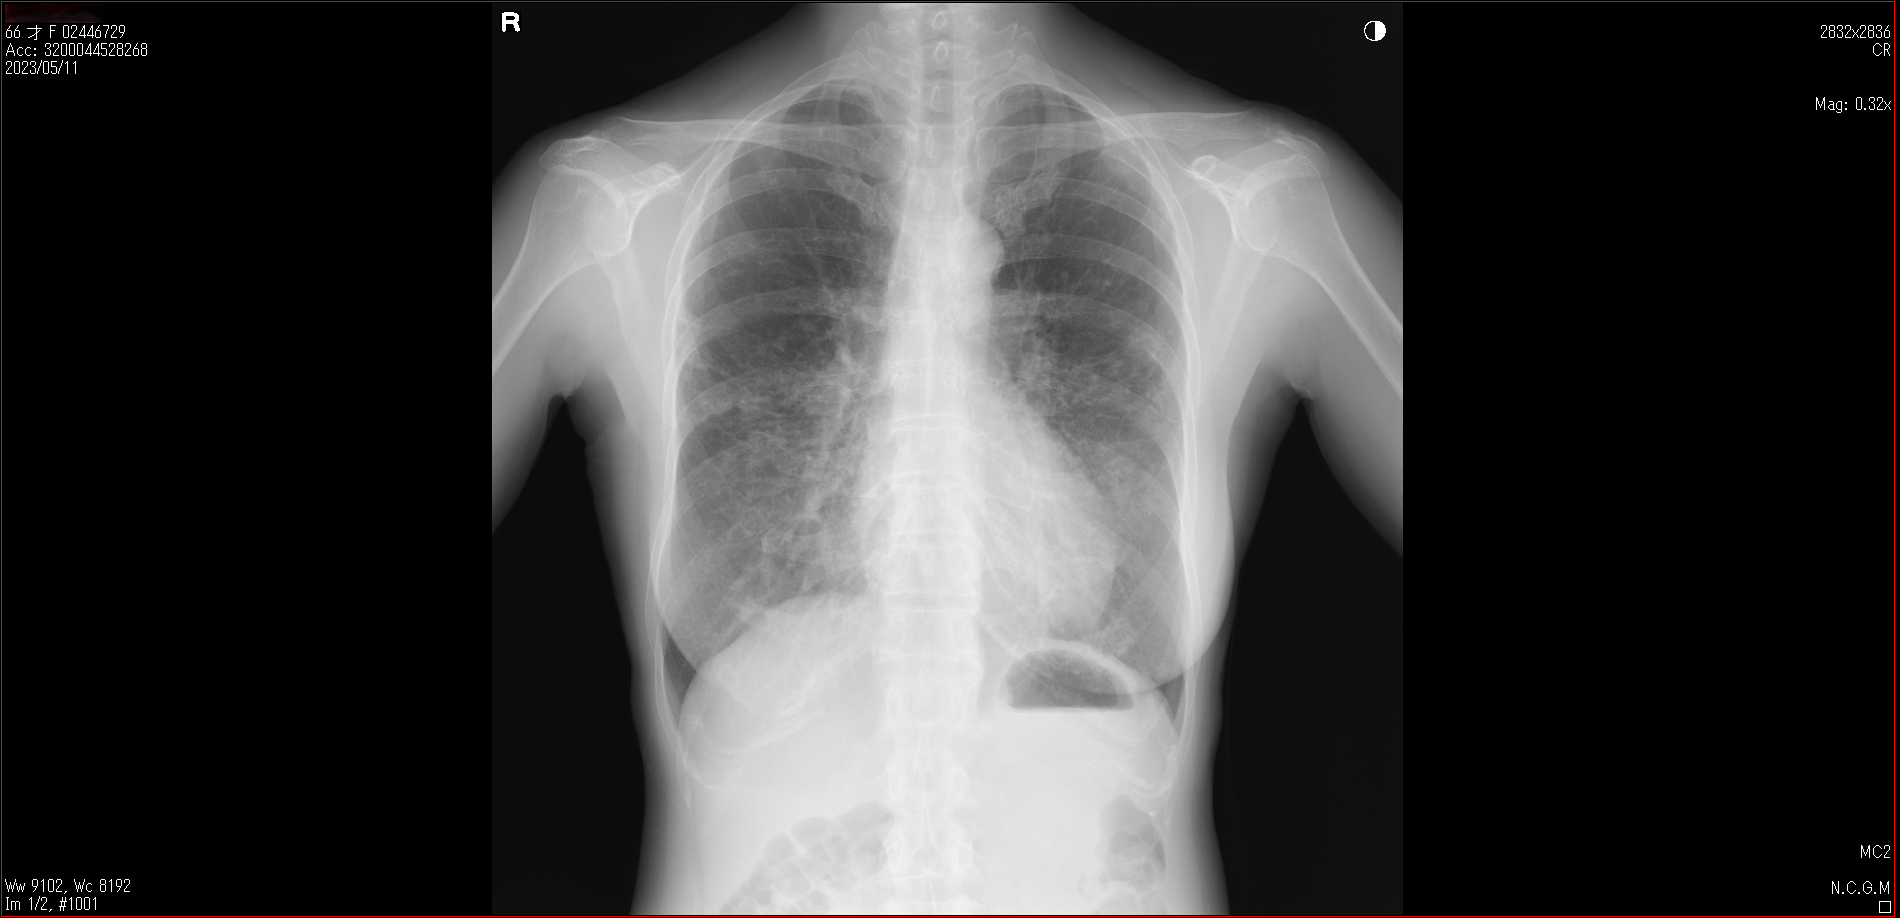

肺X線画像

- 2023.05.11 要観察と診断された画像(国立系病院)